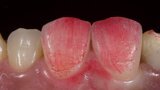

Esthetic Rehabilitation of Maxillary Anterior Teeth: Dr Sanjay Sah